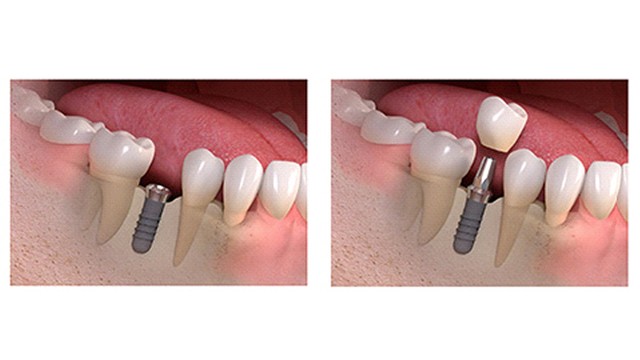

Following surgery and the adequate healing time the proper implant crown and abutment are attached to the implant for the final prosthesis.